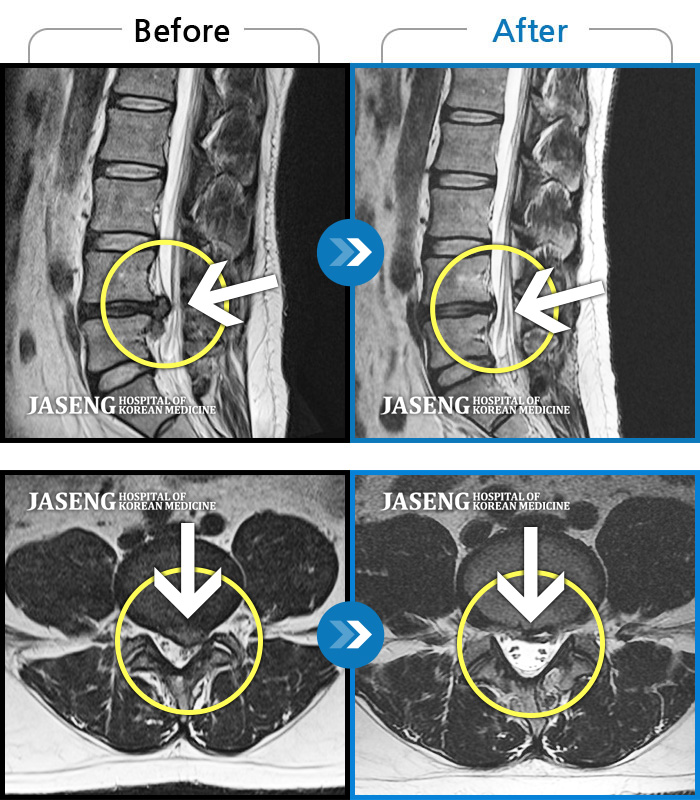

[뱸] 19.11.28~25.05.06

ȯںп Ǹ ǿ ԿǾ, ο ġ ۿ Ƿ ġḦ Ͻñ ٶϴ.